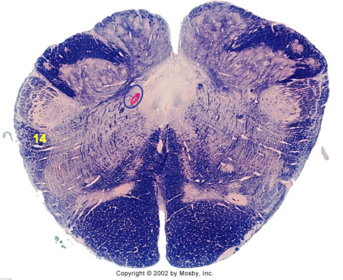

| Nucleus gracilis | |

| Accessory nucleus | |

| Medial longitudinal faciculus | |

| Pyramidal decussation | |

| Medullary pyramids | |

| Anterior spinocerebellar tract | |

| ALS | |

| Posterior spinocerebellar tract | |

| Spinal tract of V | |

| Spinal nucleus of V | |

| Nucleus cuneatus | |

| Fasciculus cuneatus | |

| Fasciculus gracilis | |

| Central canal | |